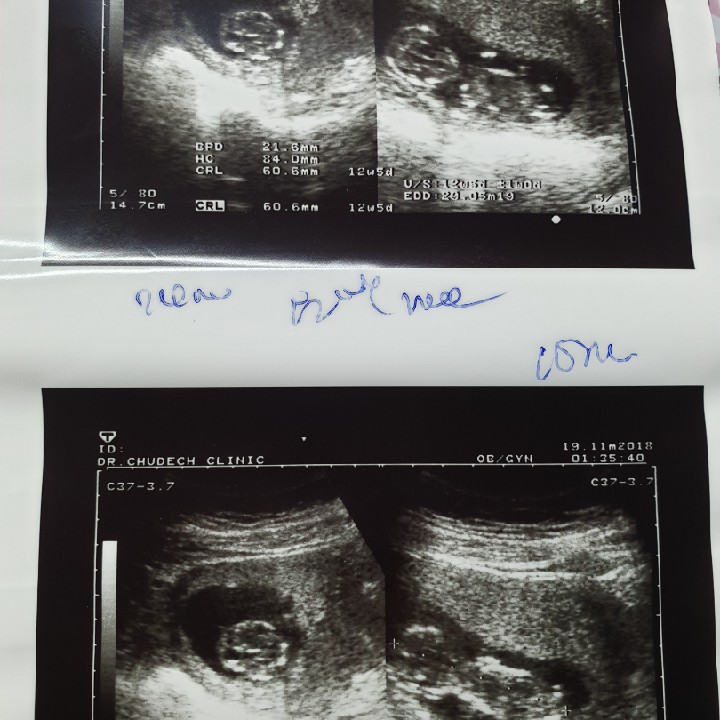

เห็นชัดหมดเหมือนกันคะ แต่ยังไม่เห็นเพศ13w

บ้านนี้ชัดตั้งแต่11w3d แขนขาดั้งมาครบแล้วค่ะ

ของเราซาวด์ตอน 11 week 5 day ก็ชัดมากเลยจ้า ☺️